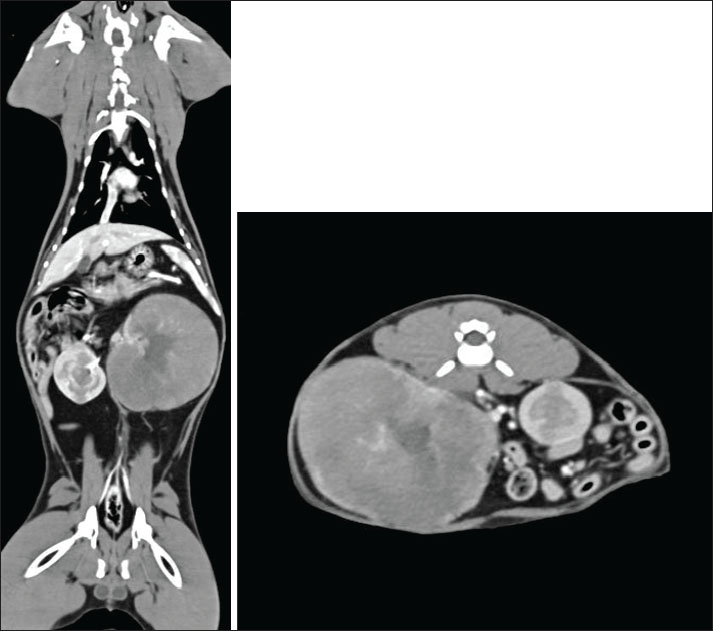

Hematology (Table 1), full biochemistry profile (Table 2), and urine protein to creatinine ratio (UPC) (Table 3) showed no significant abnormalities. Immunodeficiency virus and feline leukemia virus were both negative on the SNAP test (4Dx Plus; IDEXX Laboratories, Westbrook, ME). CT angiography of the thorax and abdomen revealed left renomegaly measuring approximately 80 mm in width and 65 mm in height and 90 mm in length with a markedly deformed structure, no corticomedullary definition, and a large lobulated expansile appearance (Fig. 1). The mass effect led to severe lateral intestine displacement into the right abdomen and craniolateral displacement of the spleen, which curled in the left cranial abdomen. The right kidney was mildly enlarged, approximately 50 mm in length, with several expansile, rounded lesions within the cortex and medulla. The rest of the CT examination was unremarkable. Ultrasound-guided fine needle angiography aspirates of the mass arising from the left kidney revealed a cell population of large-cell lymphoma (Fig. 2). A Cyclophosphamide, vincristine, prednisolone and vinblastine (COVP) protocol was initiated. This comprises a modified COP protocol with vinblastine addition (Pui Yung Anna., 2025). Complete remission was achieved after the second week of the COVP protocol. No significant AEs attributed to chemotherapy were reported during the chemotherapy course.

Fig. 1. Soft tissue window CT scan of the left coronal and right axis. The left kidney is markedly enlarged and measures approximately 80 mm in width, 65 mm in height, and 90 mm in length. It has a markedly deformed structure with no cortical medullary definition and a large lobulated expansile appearance. The cortex and medullary show reduced contrast enhancement, whereas the irregular peripheral rim of the tissue shows increased contrast enhancement. It retains a central area resembling a renal pelvis, where the left renal artery and vein are seen to enter; however, no accumulation of contrast medium is seen. The left kidney has a mass effect with severe lateral displacement of the intestines into the right abdomen. It also causes craniolateral displacement of the spleen, which is curled in the left cranial abdomen. The right kidney is mildly enlarged, measuring approximately 5 cm in length. It has several expansile rounded lesions within the cortex and medulla that mildly deform the external contour of the kidney. They are similar to attenuation to the medulla precontrast (approximately 40 HU) but show markedly reduced contrast enhancement.